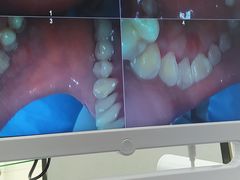

• 牙博士口腔品牌连锁(杨浦店)

• -牙博士口腔品牌连锁(杨浦店)

日料与海鲜共舞 | 21-03-03